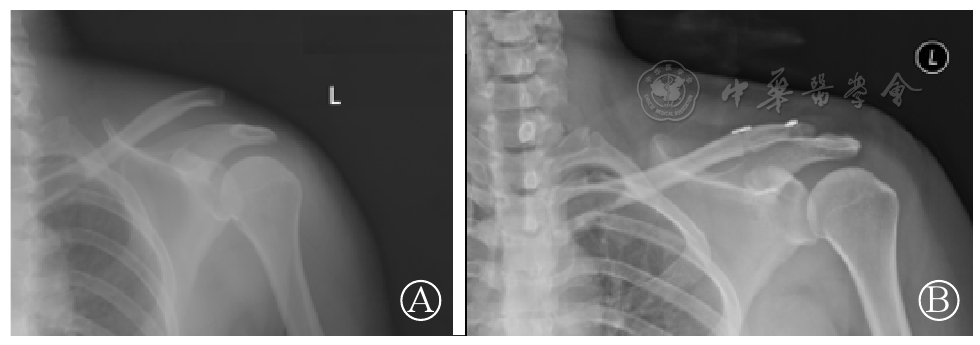

图1 钩板组术前(图A)、术后(图B)X线片